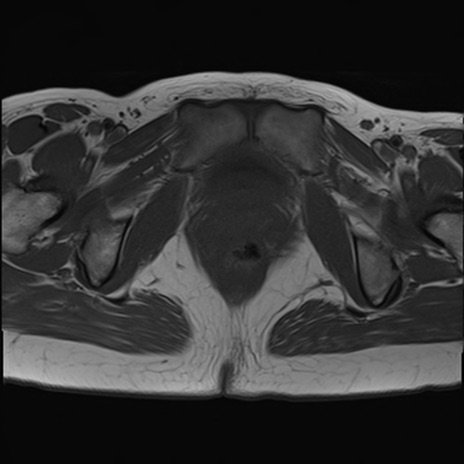

症例39 T1WI(横断像)

MRI(4日後)